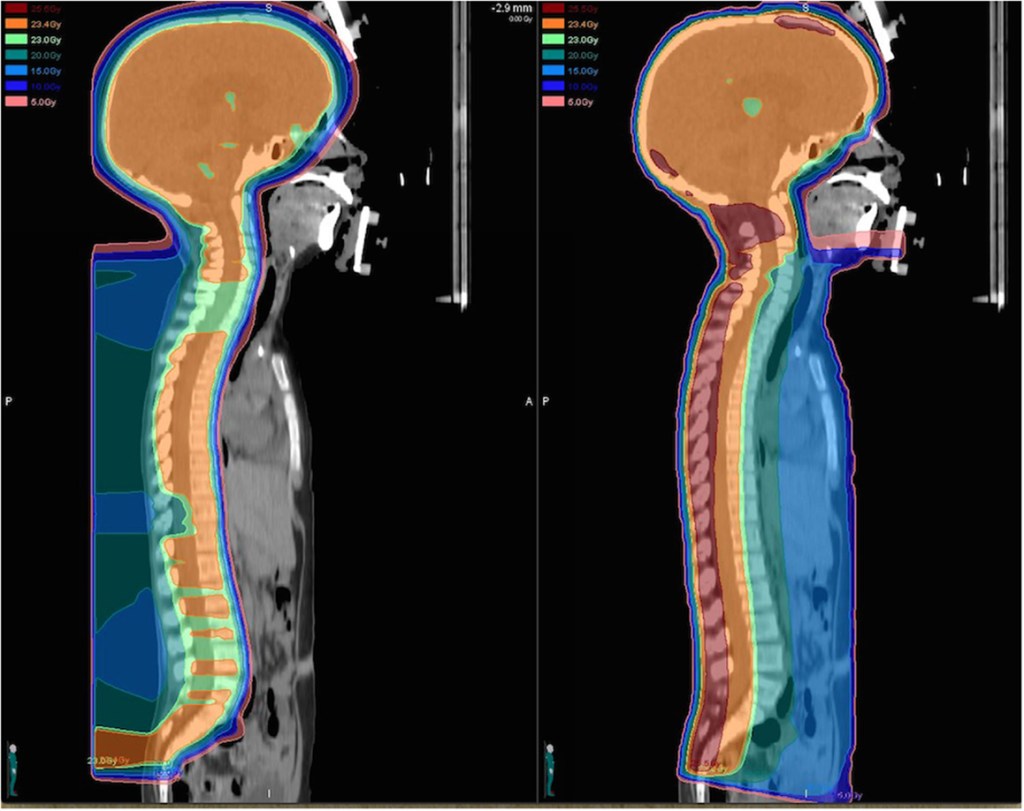

There are two major types of external beam radiation: photon (or X-ray) based radiation and particle (proton) radiation. Photon radiation is the most widely available modality with which many cancer patients are treated. Proton radiation, however, has recently garnered attention for its physical characteristics that allow the radiation dose to be localized to the tumor target while better sparing the healthy nearby tissues. In contrast to photons, there is no exit dose to tissues beyond the tumor.

Proton radiation is less widely available and is also very expensive. Long-term health outcomes research is required to determine if the properties of proton radiation translate to an improvement in health among survivors of childhood brain tumors. Our study involves a comparison of neurocognitive and health-related quality of life outcomes among patients treated with proton radiation at Massachusetts General Hospital (MGH) and patients treated with photon radiation who are followed at Emory University/Children’s Healthcare of Atlanta (CHOA).